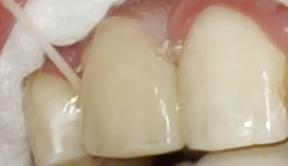

Al examen clínico intraoral se evidenció en la pieza, motivo de consulta, una alteración del desarrollo

dentario de forma, asemejando tener dos coronas en una sola pieza dentaria, unidas parcialmente en el tercio medio y cervical, delimitado por un surco central proveniente de la unión cementoesmalte, presentando una corona disto vestibular y otra mesiopalatina, hacia el borde incisal las coronas están separadas, también se evidencia a nivel del surco una caries de esmalte con cambio de coloración marrón (Fig. 1.A). A nivel de la cara palatina de la pieza 1.2 se evidencia la presencia de una cúspide accesoria en la corona mesiopalatina la misma que se denomina cúspide en garra (Fig. 1.B).

Figura Nº1 A. Fotografía intraoral en oclusión, señalando la pieza (1.2) note el surco vestibular con cambio de coloración. B. Fotografía intraoral oclusal se observa en la corona mesiopalatina la cúspide en garra.

Fuente: Elaboración propia, octubre 2021.